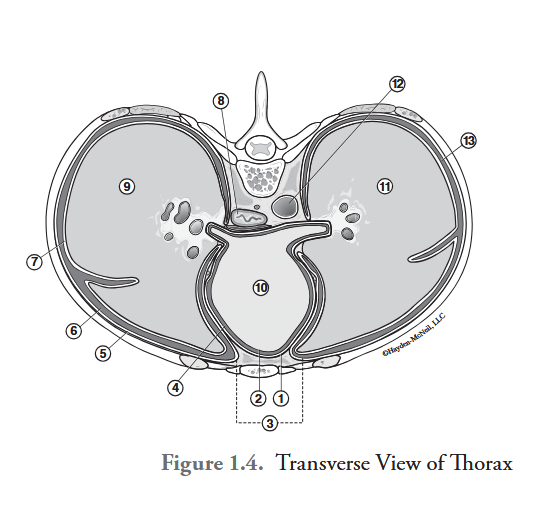

What is labeled #1?

parietal pericardium

What is labeled #2?

visceral pericardium (epicardium)

What is labeled #3?

mediastinum

What is labeled #4?

pericardial cavity

What is labeled #5?

parietal pleura

What is labeled #6?

right pleural cavity

What is labeled #7?

visceral pleura

What is labeled #8?

esophagus

What is labeled #9?

right lung

What is labeled #10?

heart

What is labeled #11?

left lung

What is labeled #12?

descending aorta

What is labeled #13?

left pleural cavity